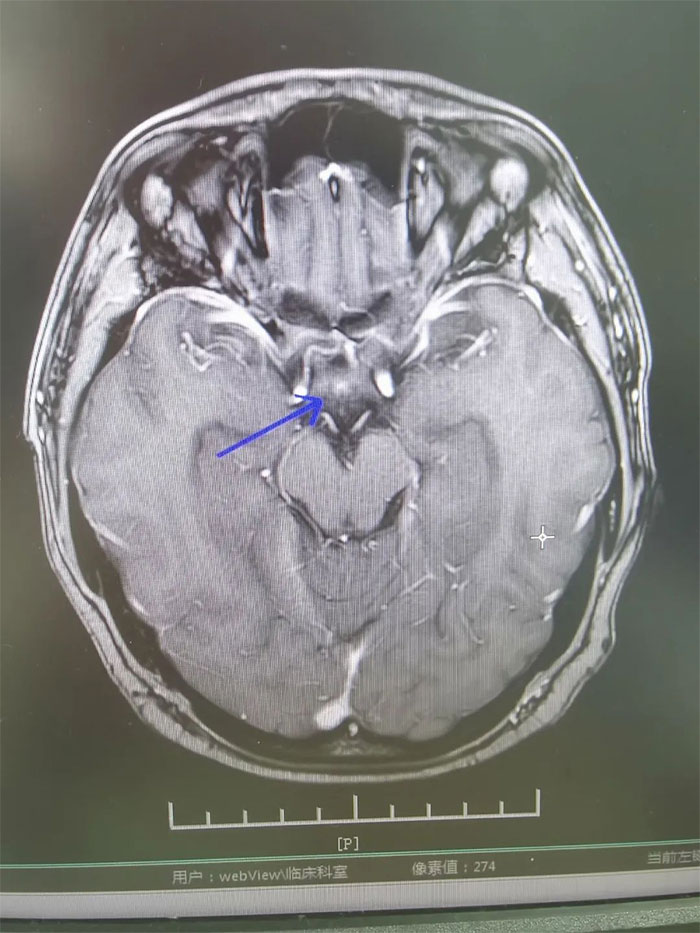

▲ 放疗后复查,病灶明显缩小

经过一个完整疗程的放疗,患者没有出现明显并发症,头痛、恶心呕吐症状得到缓解。复查MRI,影像显示病灶明显缩小,梗阻性脑积水消失。进一步完善检查评估后,小刚已顺利出院。眼见短时间内病情即得到控制,小刚对生活又重拾信心,表示一定会以积极的心态面对人生。